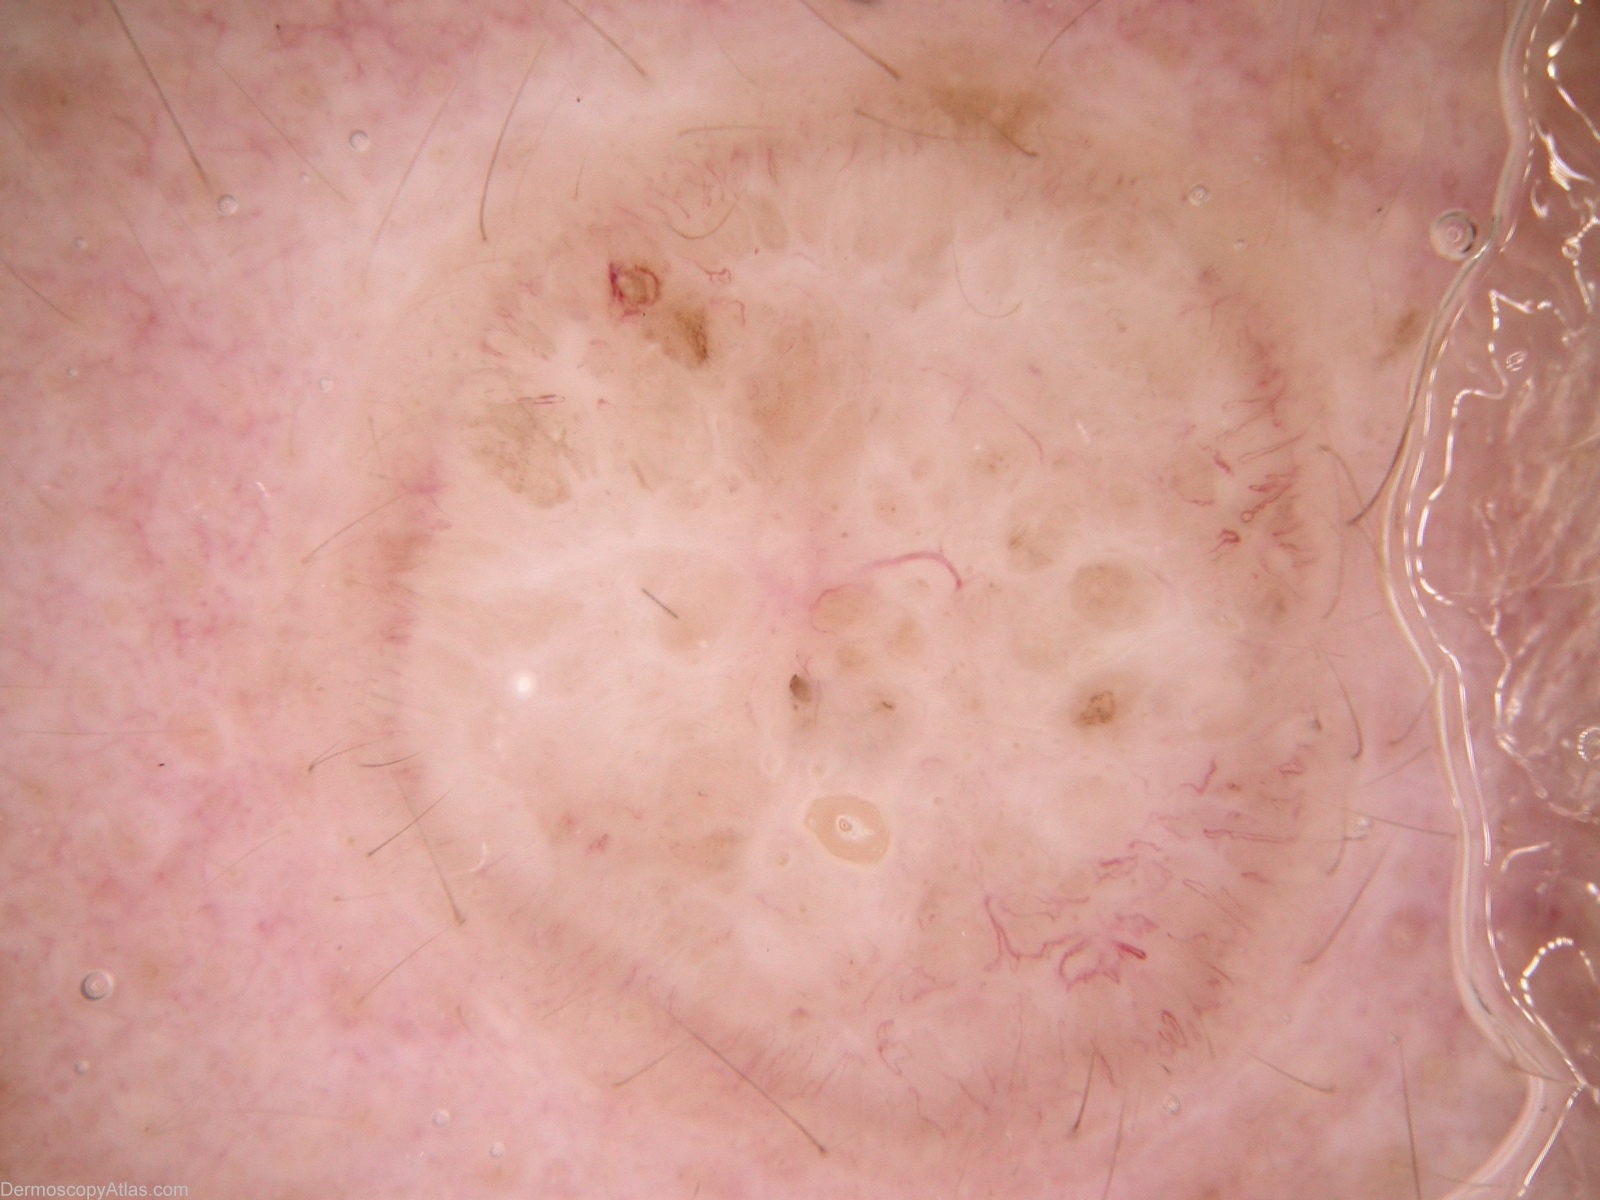

Site: Forehead

Diagnosis: BCC - Solid

Type: Mixed

Submitted By: Alan Cameron

Description: Dermlite Fluid non-polarising. Vessels are concentrated peripherally, either thin hairpin or linear. I cannot convincingly call the lightly pigmented regions either blue/grey ovoid nests or leaf-like areas. While arborising vessels are diagnostic of BCC, BCCs may have many other vessel patterns

History: Slowly enlarging plaque on forehead.